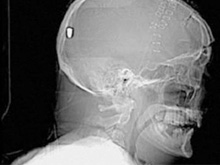

В Британии врачи нашли у пациента пулю в голове13.05.10 13:07 Прочтений новости 1609 Общество В Британии у пациента, который поступил в клинику с подозрением на инсульт, врачи обнаружили пулю в голове. Но остается неизвестным, как мужчина получил ранение.Рентгеновские снимки головы показали, что в полости черепа находится инородный предмет. Мужчине сделали томографию головы, и врачи установили, что этим предметом является пуля. Как сообщается, 19 апреля 61-летний Питер Хесфорд упал во время работы у себя в саду. Позже его обнаружила жена, которая вызвала скорую. Мужчина оставался в сознании, но не мог говорить. Медики, прибывшие на место, заподозрили у Питера Хесфорда инсульт и доставили его в Больницу Уитеншо. Эксперты по баллистике, изучив снимки пациента, пришли к выводу, что пуля, застрявшая в затылочной области, могла попасть туда через глаз. Но мужчина не помнит, что именно с ним произошло. Врачи попытались удалить пулю, однако это оказалось невозможным из-за ее положения по отношению к окружающим структурам. Пациент остается в больнице, а его состояние расценивается как стабильное. Комментарии (всего 0)